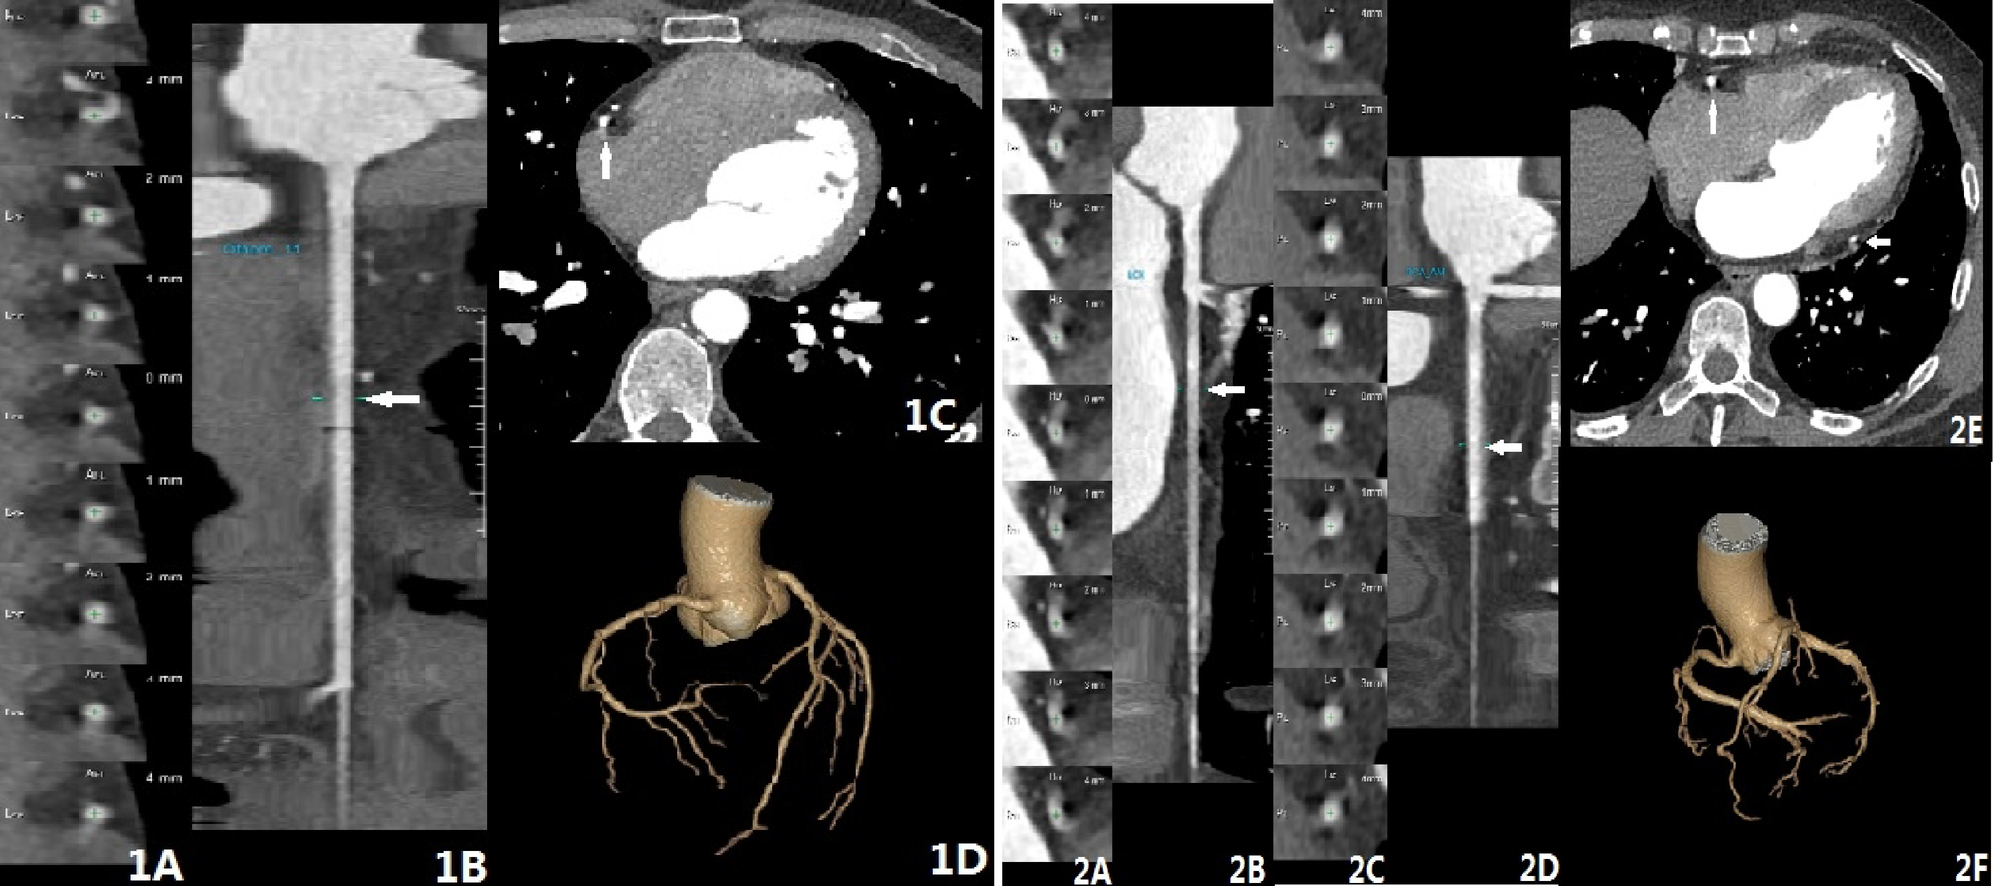

Fig. 2

CCTA examination showed different types of artefacts and scoring results. Patient 1 (1 A, 1B, 1 C, 1D) – 1 A shows the axial image at the position marked by the arrow in 1B (RCA curved CPR reconstruction). 1 C is the CCTA axial image, where the contour of the RCA segment is unclear, with a comet-tail blur at the arrow position. 1D (VR image) shows the overall continuity of the CCTA with no layering or motion artefacts, indicating that only the RCA segment exhibits artefacts, with a score of 4. Patient 2 (2 A, 2B, 2 C, 2D, 2E, 2 F) – 2 A and 2 C correspond to 2B (RCA curved CPR reconstruction) and 2D (LCX curved CPR reconstruction) at the marked positions in the axial images. 2E is the CCTA axial image, where the contours of both the RCA and LCX vessels are unclear, with comet-tail blur present. 2 F (VR image) demonstrates the overall continuity of the CCTA with no layering or motion artefacts, indicating artefacts in both the RCA and LCX segments, resulting in a score of 3.